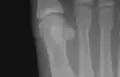

The first metatarsal. (Left.)

Like the four other metatarsals, it can be divided into three parts: base, body and head. The base is the part closest to the ankle and the head is closest to the big toe. The narrowed part in the middle is referred to as the body of the bone. The bone is somewhat flattened, giving it two sides: the plantar (towards the sole of the foot) and the dorsal side (the area facing upwards while standing).[1]

The first metatarsal articulates (forms joints) with the medial cuneiform and to a small extent with the intermediate cuneiform bone.[2] Its proximal articular surface is large and kidney-shaped; its circumference is grooved, for the tarsometatarsal ligaments, and medially gives insertion to part of the tendon of the tibialis anterior.

The head is large; on its plantar surface are two grooved facets on which the sesamoid bones glide; the facets are separated by a smooth elevation.